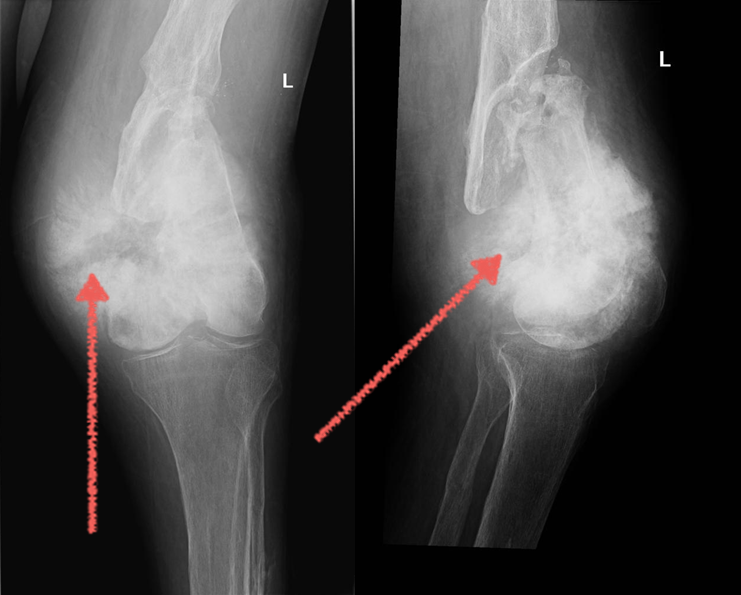

Остеосаркома – это злокачественная опухоль, происходящая из костной ткани. Отличается склонностью к бурному течению и раннему метастазированию. На начальных стадиях проявляется локальной болью, похожей на боли при ревматизме. В дальнейшем появляется припухлость, ограничение движений в расположенном поблизости суставе. Боли становятся резкими, невыносимыми. Возникают метастазы.

Полгода назад в компанию МедикаТур обратились родители мальчика, который болел остеосаркомой. В Киргизии, где семья живёт, не могли ему помочь.

В МедикаТур после изучения его медицинских выписок и анализов было предложено лечение в крупнейшей клинике Индии "Max Hospitals".

Операция прошла успешно и сейчас мальчик уже вернулся домой к обычной жизни.